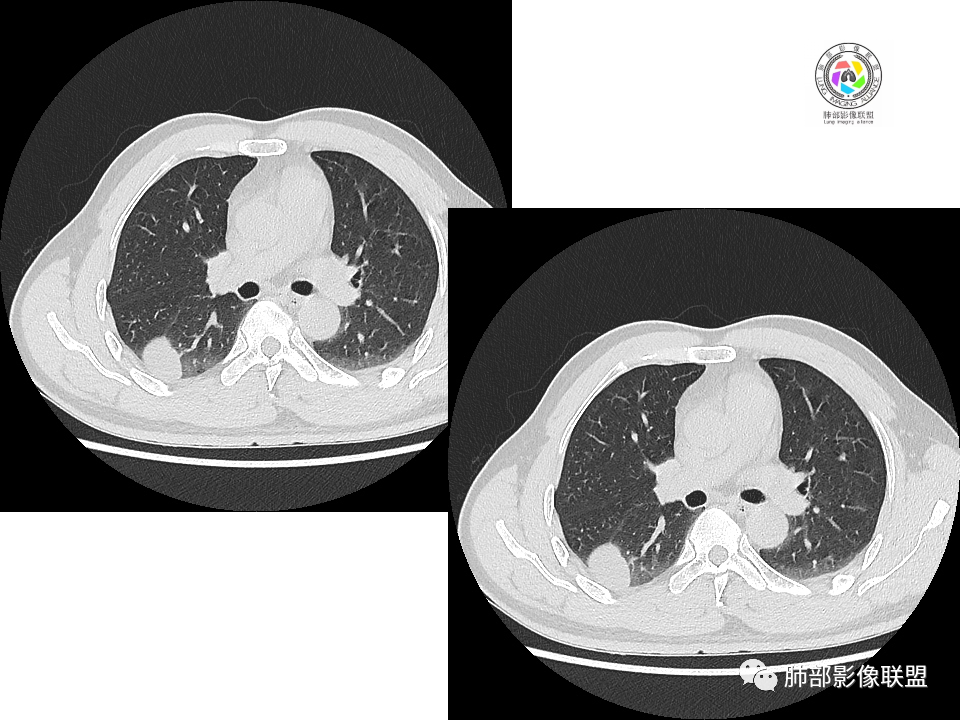

右肺下叶占位,胸膜下,与胸膜关系密切;

密度均匀;糊墙,边缘膨隆为主;

部分血管推移。

支气管如何?

浅分叶

这个结节呢?

这两个病灶的密度、强化、形态、边缘、与血管的关系类似;还是一元论吧。

1.边缘光整干净,大病灶缺乏坏死等,不符合鳞癌影像学特征。尽管有吸烟史,还是偏年轻。

2.边缘光整,会是小细胞癌或是大细胞癌吗?小细胞癌的肺门纵隔淋巴结增大往往十分夸张,该患者不符合。

注意,基底段支气管血管束旁的小结节影,即便是淋巴结,也与背段病灶引流途径不符。